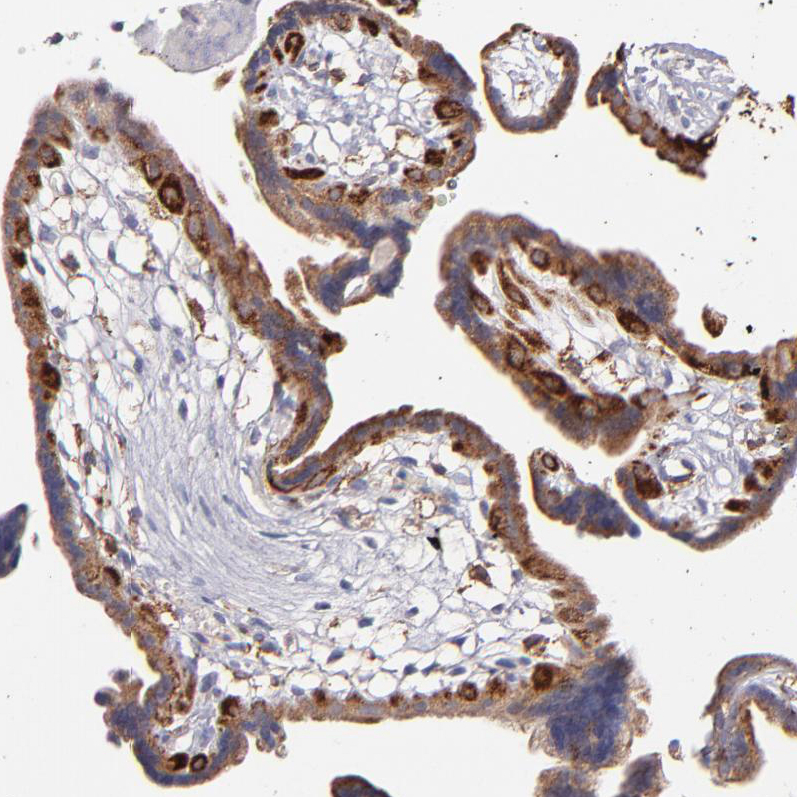

Immunohistochemistry analysis in human placenta and skeletal muscle tissues using HPA002318 antibody. Corresponding GLDC RNA-seq data are presented for the same tissues.